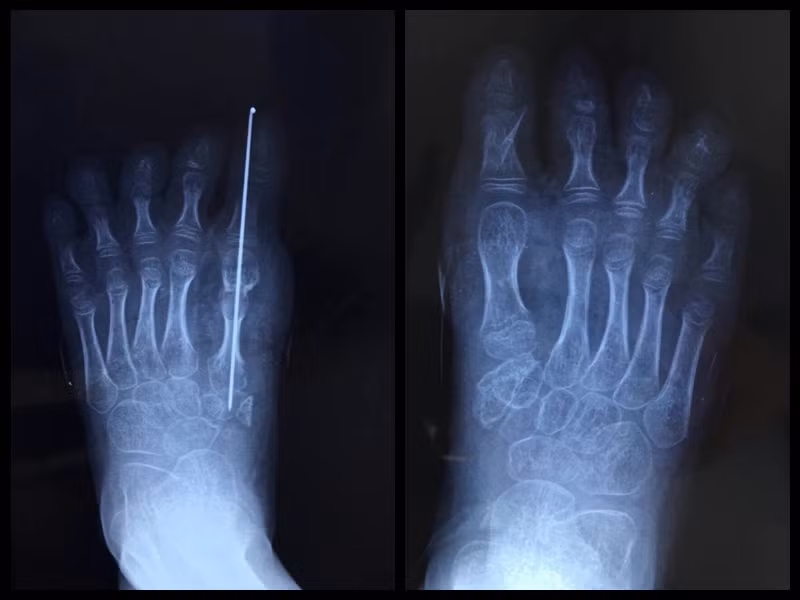

Cuộc phẫu thuật ban đầu được thông báo là rất phức tạp, các bác sỹ đã phải lấy từng ngón xương chân và dây thần kinh ghép lại thành một ngón chân hoàn chỉnh. Tuy nhiên, cha mẹ bé gái 4 tuổi cũng được các bác sỹ cảnh báo, việc khắc phục dị tật bẩm sinh có nguy cơ biến dạng cao, trong trường hợp ngón chân không thể ghép khả thi sẽ phải cắt bỏ, điều này ảnh hưởng nghiêm trọng đến đứng và đi bộ. Sau khi đánh giá rủi ro, cha mẹ bé gái quyết định phẫu thuật.

Con gái họ được đưa vào phòng mổ, gây mê. Ngón chân của bé gái 4 tuổi nhỏ nhất chỉ khoảng nửa cm, vậy nên để gắn kết các dây thần kinh động mạch, tĩnh mạch chính xác là điều cực kỳ khó.